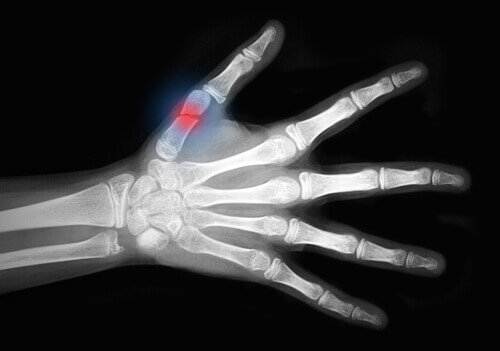

Denne sykdommen svekker beinene dine, noe som gjør dem skjøre og tilbøyelige til å knekke. Håndleddet, hofter eller ryggsøylen er de områdene som har størst risiko for å knekke.